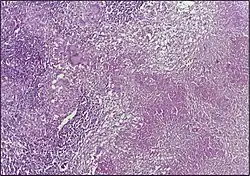

![]() | Tuberculous granuloma | Caseating granulomatous lesion with areas of amorphous granular eosinophilic necrotic debris known as caseation (on the right half) bordered by collections of epitheloid cells, Langhan giant cells and lymphocytes. | Category: Histopathology of tuberculous granuloma | Tuberculous granuloma |